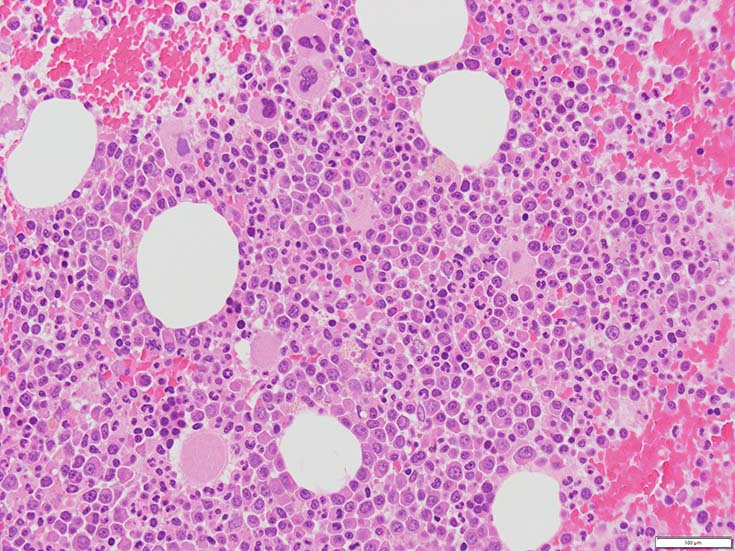

初診時の骨髄組織所見

BM-f-01HE01.jpg BM-f-01HE02.jpg BM-f-01.jpg

HE染色および, Naphtol-ASD-CAE染色した骨髄クロット組織標本-->Naphtol-ASD-CAE染色, 載せガラス法のページをみる.

70-80%のhypercellular marrow. 3系統造血細胞が認められる. Naphtol-ASD-CAE染色で赤色にそまる顆粒球系細胞増生が顕著な骨髄組織.

promyelocytesなど幼若顆粒球系細胞の集簇がみられるが, 分葉好中球他, 成熟顆粒球(Naphtol-ASD-CAE染色は薄く染まる傾向あり)も多く認められacute leukaemiaの所見ではない.

単球(Naphtol-ASD-CAE染色陰性)が密に増殖する所見は骨髄組織には認められない(*1)